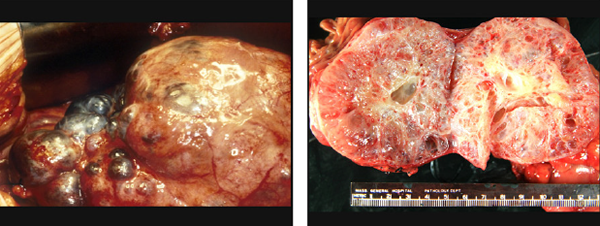

Özel bir hormon salgılamadıkları için ameliyat öncesi tanıları her zaman olanaklı değildir. Ayrıca bu ayrımın yapılması her zaman gerekli de değildir. Pankreasta eğer kistik olmayan solid bir kitle saptanırsa yaklaşım ameliyata engel özel bir durum olmadığı sürece cerrahidir. Pankreasın diğer organlarda görülebilen iyi huylu ve çıkartılması gerekmeyen bir kitlesi yoktur.

Bu nedenle fonksiyon göstermeyen tüm endokrin tümörlerde boyutlarına bakılmaksızın cerrahi olarak çıkartılırlar. En önemli avantajları 3 cm’den küçük olduklarında pankreas kanserinde olduğu gibi büyük cerrahi gerektirmeden çıkartılabilmeleridir. Ancak bölgesel lenf bezlerinde tutulum olduğu düşünülürse pankreas kanseri gibi davranılmalıdır.

Endokrin tümörler pankreas kanserine göre daha iyi seyirlidirler. Ancak onlarda uzak organlara yayılabilirler ve zaman zaman pankreas kanseri gibi seyredebilirler.